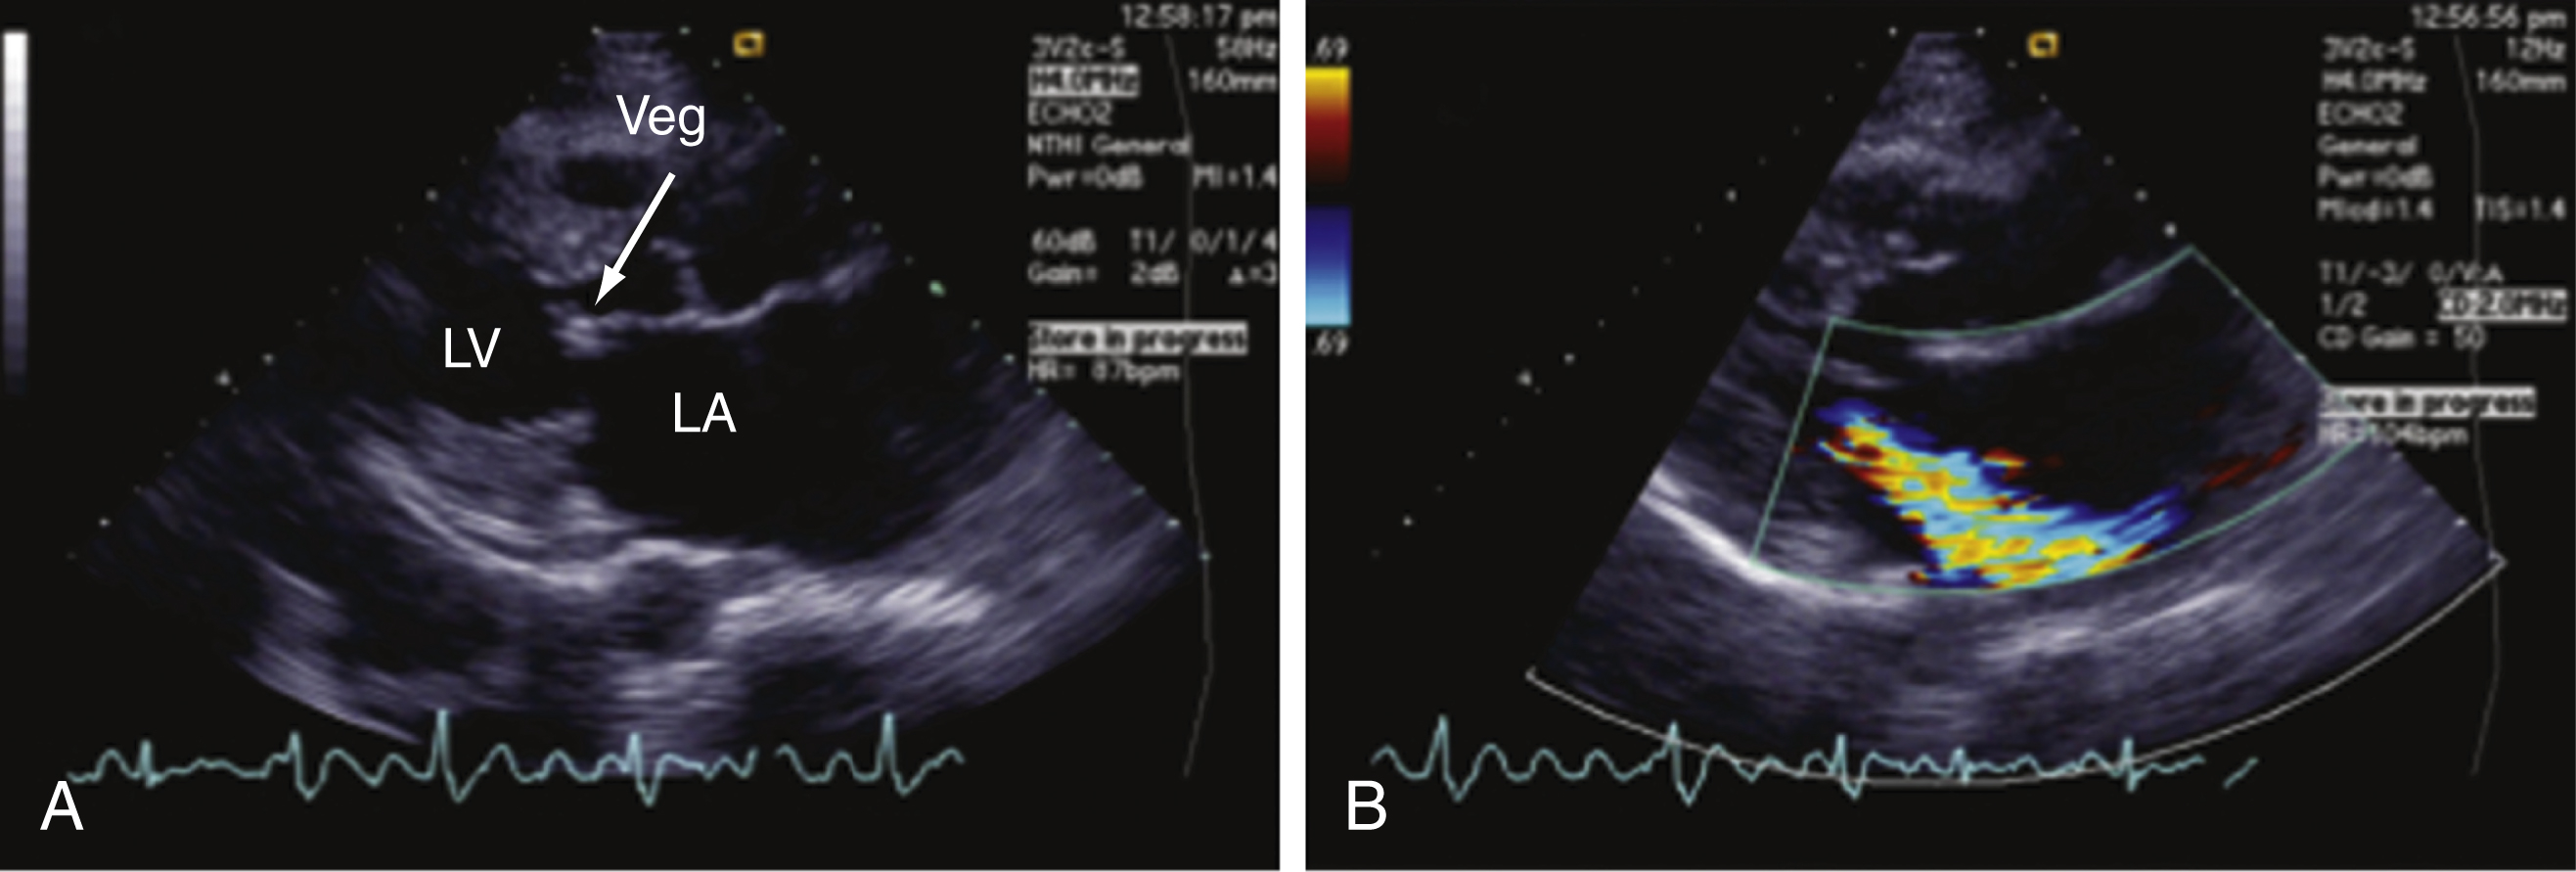

SLE is associated with a type of noninfectious endocarditis known as Libman-Sacks endocarditis ( Fig. 105.2 ). Mitral valve disease is most common, though other valves may also be affected. While the lesions formed on heart valves in this condition are more often associated with embolization than valvular dysfunction, some patients may develop valvular insufficiency that may present with shortness of breath, fatigue, or, in rare severe cases, pulmonary edema.

Noninfectious endocarditis, known as a Libman-Sacks lesion, in a 56-year-old woman with systemic lupus erythematosus (SLE), a heart murmur, and dyspnea on exertion. (A) A parasternal long-axis view of the heart; a vegetation (Veg) is identified (arrow) on the mitral valve. (B) When color flow is superimposed on the valve, moderate to severe mitral regurgitation can be seen as a color jet entering the left atrium during systole. LA, Left atrium; LV, left ventricle.

Courtesy Martin Goldman, MD, Mount Sinai School of Medicine.